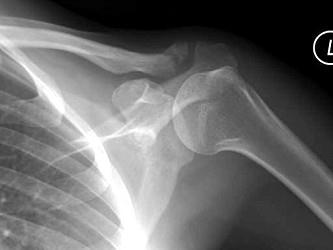

图示骨折易发生何种损伤 ( )A、胸锁乳突肌B、副神经损伤C、膈神经损伤D、颈神经根E、臂丛神经损伤

问题 图示骨折易发生何种损伤 ( )

选项 A、胸锁乳突肌 B、副神经损伤 C、膈神经损伤 D、颈神经根 E、臂丛神经损伤

答案 E